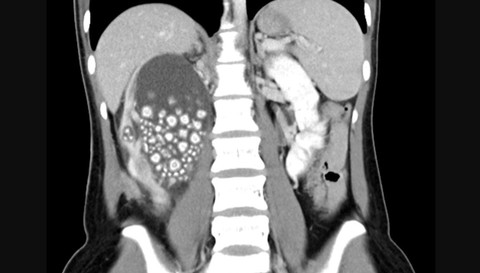

Penampakan batu ginjal di tubuh seorang wanita di Tainan, Taiwan.  Foto: Chi Mei Hospital

Dilaporkan ET Today, wanita bernama Xiao Yu dilarikan ke Rumah Sakit Chi Mei di Tainan dengan gejala demam dan nyeri hebat di punggung bawahnya. Hasil rontgen menunjukkan di ginjalnya ada ratusan butir seperti kelereng yang diidentifikasi sebagai batu ginjal kecil.

Dokter lantas memberinya antibiotik dan melakukan operasi untuk menghilangkan batu ginjal tersebut. Menurut tim medis, batu ginjal itu mirip dengan "roti kukus kecil". Setelah prosedur operasi dilakukan, dokter menemukan lebih dari 300 batu ginjal di tubuh pasien, ukurannya antar berdiameter 0,5 cm hingga 2 cm.